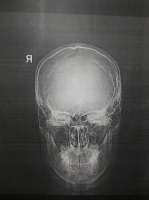

>>493043

Вот мрт. Я не хотел здесь никому навязываться, так что отвечай по желанию.

Кажется, к снимкам сопровождались комментарии, но я их не помню и видел вскользь. Возможно только они и нужны, а не снимки

>>493069

мда, загуглил и похоже это не мрт

>>493071

Совершенно верно. Это рентгеновские снимки и информацию они дают (почти) только о состоянии костей.